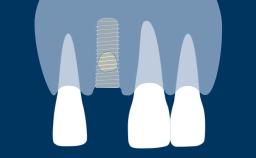

In this clinical case, the implant-supported crown replacing the missing upper right central incisor has achieved a satisfactory result with good symmetry of both the peri-implant mucosal tissues and the prosthesis, when compared with the conventional prostheses on the surrounding teeth.

However, the same level of outcome has not been achieved in this case, where significant recession of the facial mucosa has exposed the underlying abutment, resulting in an unesthetic asymmetry.

- describe how prosthesis design and fabrication can result in esthetic complications

- describe how implant positioning can lead to esthetic complications